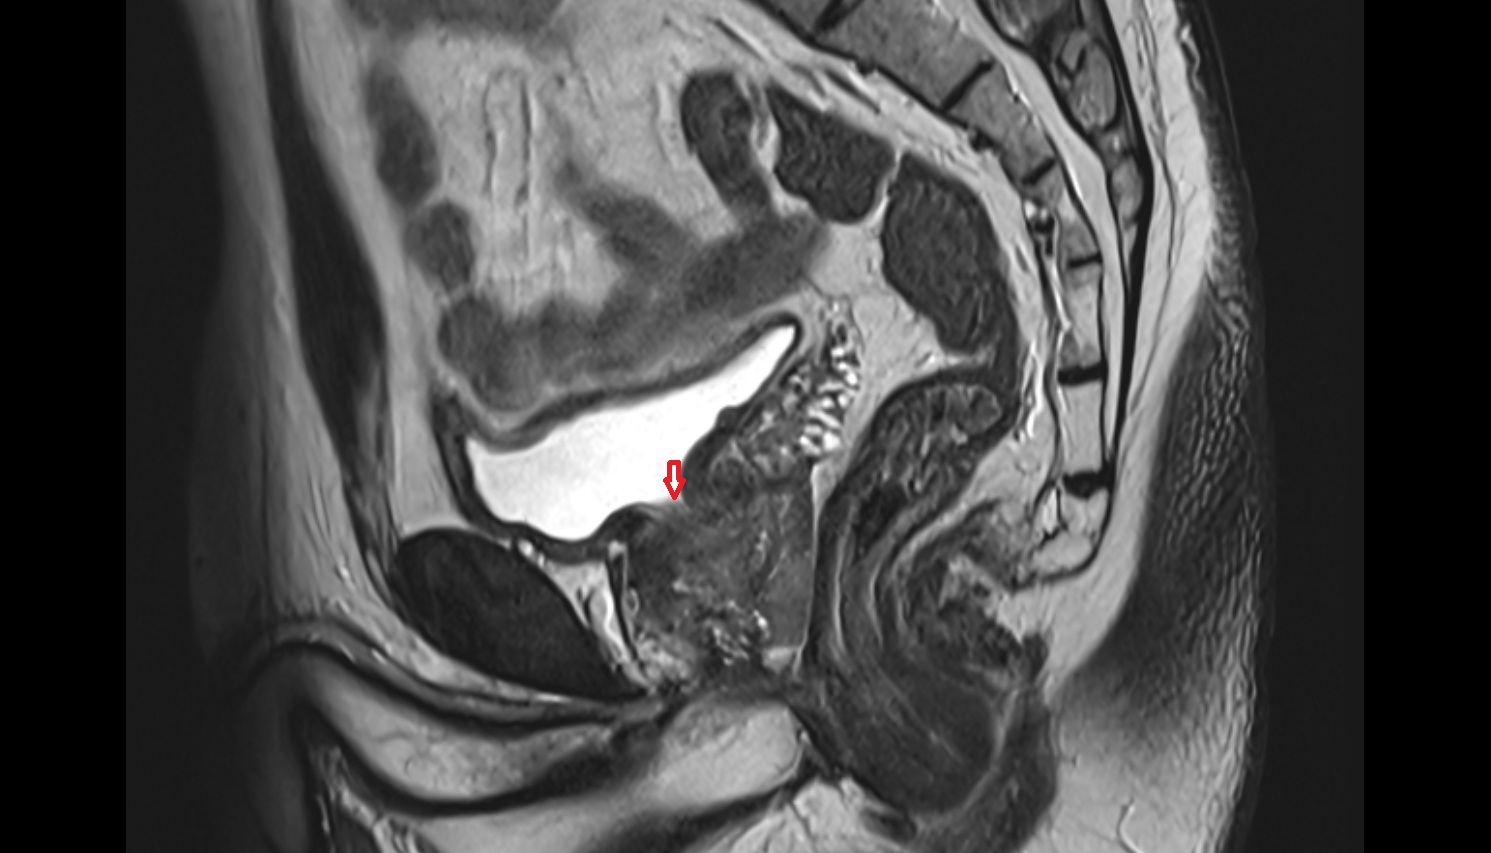

- Uterus

- Body of uterus

- Fundus of uterus

- Cervix of uterus

- Isthmus of uterus

- Vagina

- Rectum

- Urinary bladder

- Vesicouterine pouch

- Rectouterine pouch (pouch of Douglas)